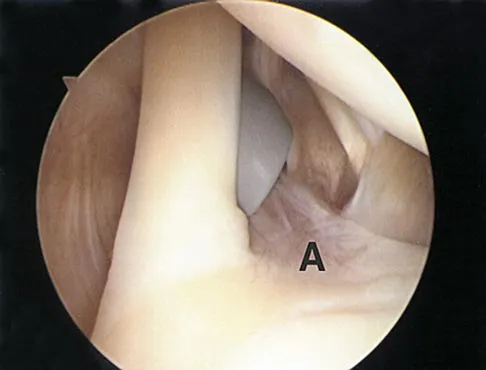

Question 6:

Figure 19 shows an arthroscopic view from the anterior lateral portal of the knee looking into the suprapatella pouch. The use of an electrothermal device during this procedure most commonly causes significant postoperative complications by damaging which of the following structures?

Correct Answer: Superior lateral geniculate artery

Explanation:

While it is possible to damage any of these structures, unrecognized intraoperative laceration without adequate coagulation of the superior lateral geniculate artery is common. This can result in significant postoperative hemarthrosis and a return to surgery when bleeding cannot be controlled. Cash JD, Hughston JC: Treatment of acute patella dislocation. Am J Sports Med 1988;16:244-249.